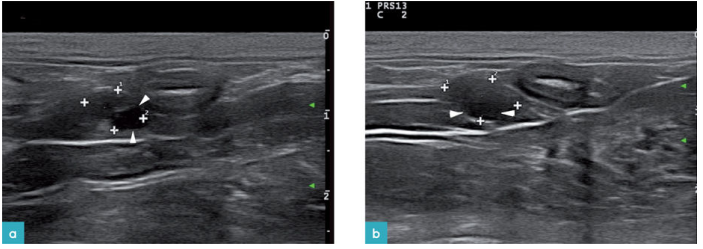

公猫生殖系统的超声扫查不如公犬的扫查常见,其数据图像较为少见,难以建立正常标准数据库。睾丸的回声细致均匀,睾丸白膜为一高回声薄的边界样结构。睾丸纵膈在矢状面上为中心高回声亮线,在横截面上为中心高回声亮点(图2)。